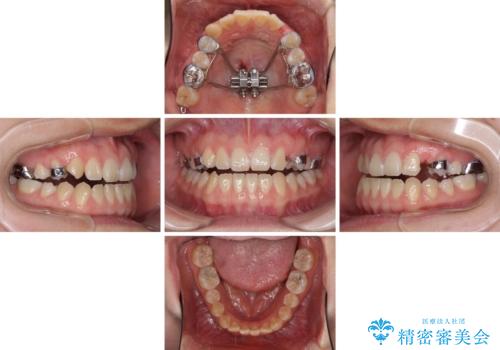

受け口で開咬を急速拡大装置とインビザラインで改善 欠損部分はインプラントにて補綴治療

上顎歯列が狭窄していたため、急速拡大装置により上顎骨を側方に拡大し、その後インビザラインにて矯正治療を行うこととしました。

矯正治療と並行してインプラントによる補綴治療を行うこととしました。

矯正治療が終わるタイミングに合わせてインプラントの埋入を行っていたので、矯正治療を終了すると同時にセラミック補綴治療を行えました。